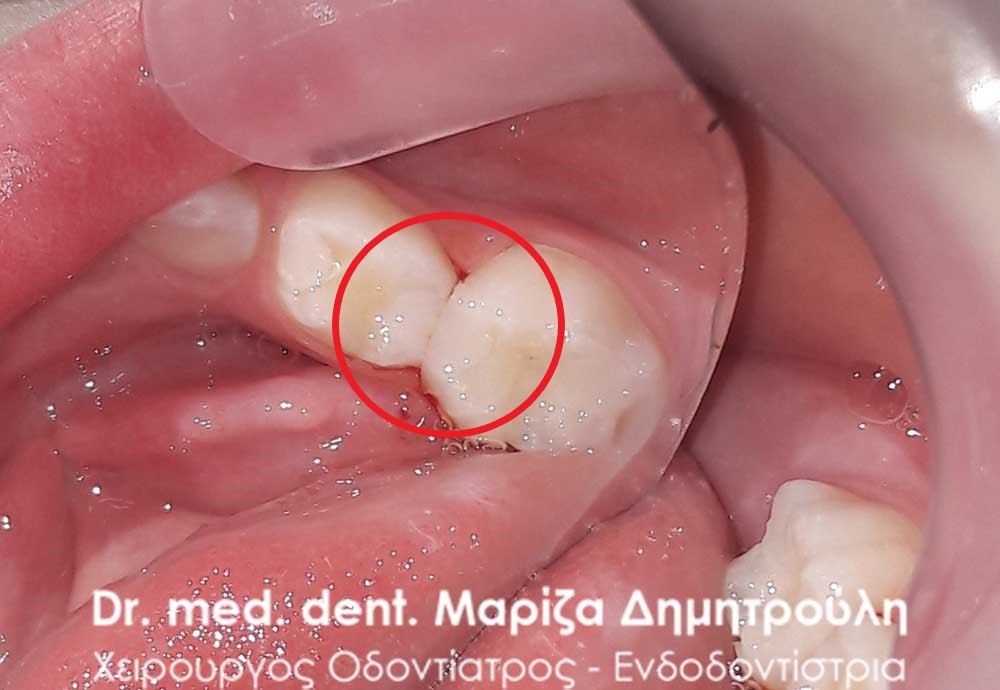

Dental filling of primary tooth

AFTER